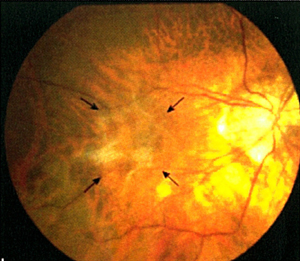

黄斑点视网膜前膜增生(图2)是本港常见眼疾之一,治疗方法包括切除玻璃体及移除前膜。采用内界膜去皮最新治疗能让患者的视力获得改善,而接受初次手术後复发率属低。

![]() 图2:深近视人士患上黄斑点视网膜前膜病变(手术前摄)。 |